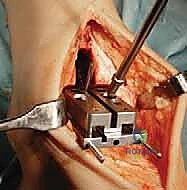

تُجرى العملية عادة تحت التخدير العام أو التخدير النصفي (الشوكي). يقوم د. هطيف بعمل شق جراحي أمامي أو جانبي (حسب التقنية المستخدمة وحالة المريض) للوصول إلى مفصل الكاحل بعناية، مع الحفاظ على الأوتار والأعصاب والأوعية الدموية المحيطة.

3. إزالة الأسطح التالفة (تحضير العظام)

باستخدام أدوات جراحية دقيقة وموجهات خاصة، يتم إزالة الغضاريف التالفة وجزء رقيق جداً من العظام المريضة من نهايتي عظمة الظنبوب وعظمة الكاحل (Talus). يتم تشكيل العظام بدقة لتتطابق تماماً مع شكل أجزاء المفصل الصناعي.

4. تركيب المفصل الصناعي (Implantation)